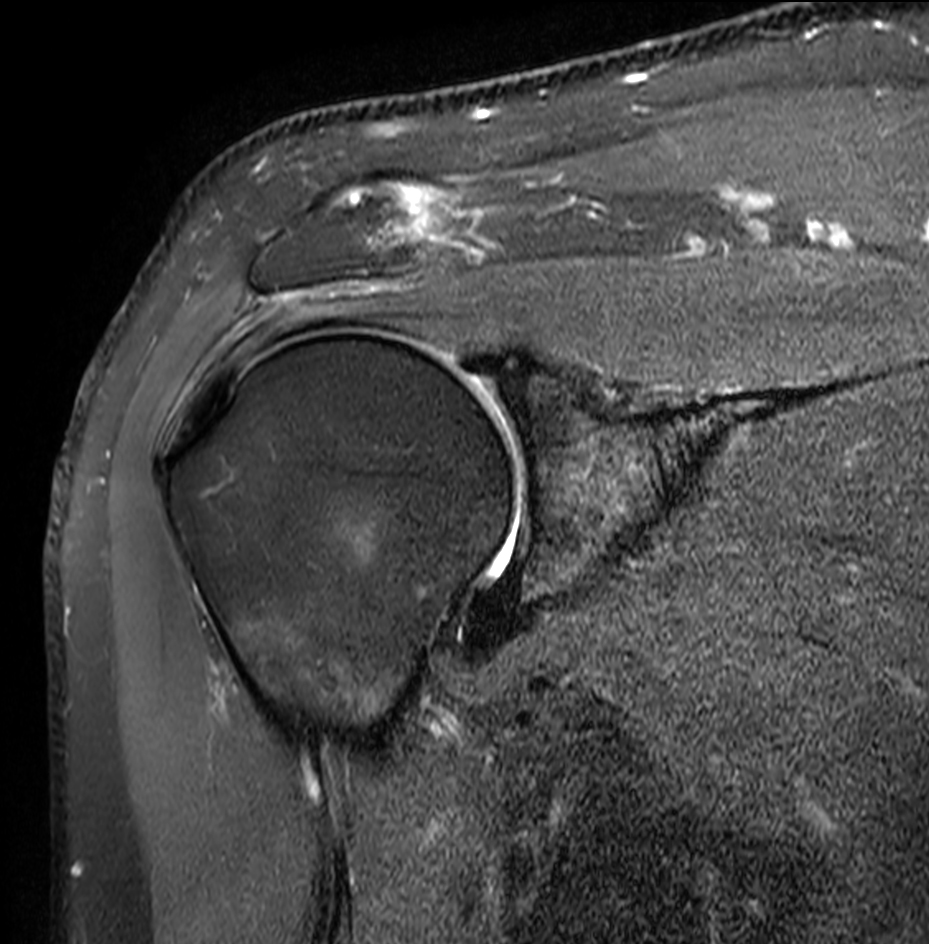

High resolution imaging with the dS 16ch Shoulder coil and Compressed SENSE